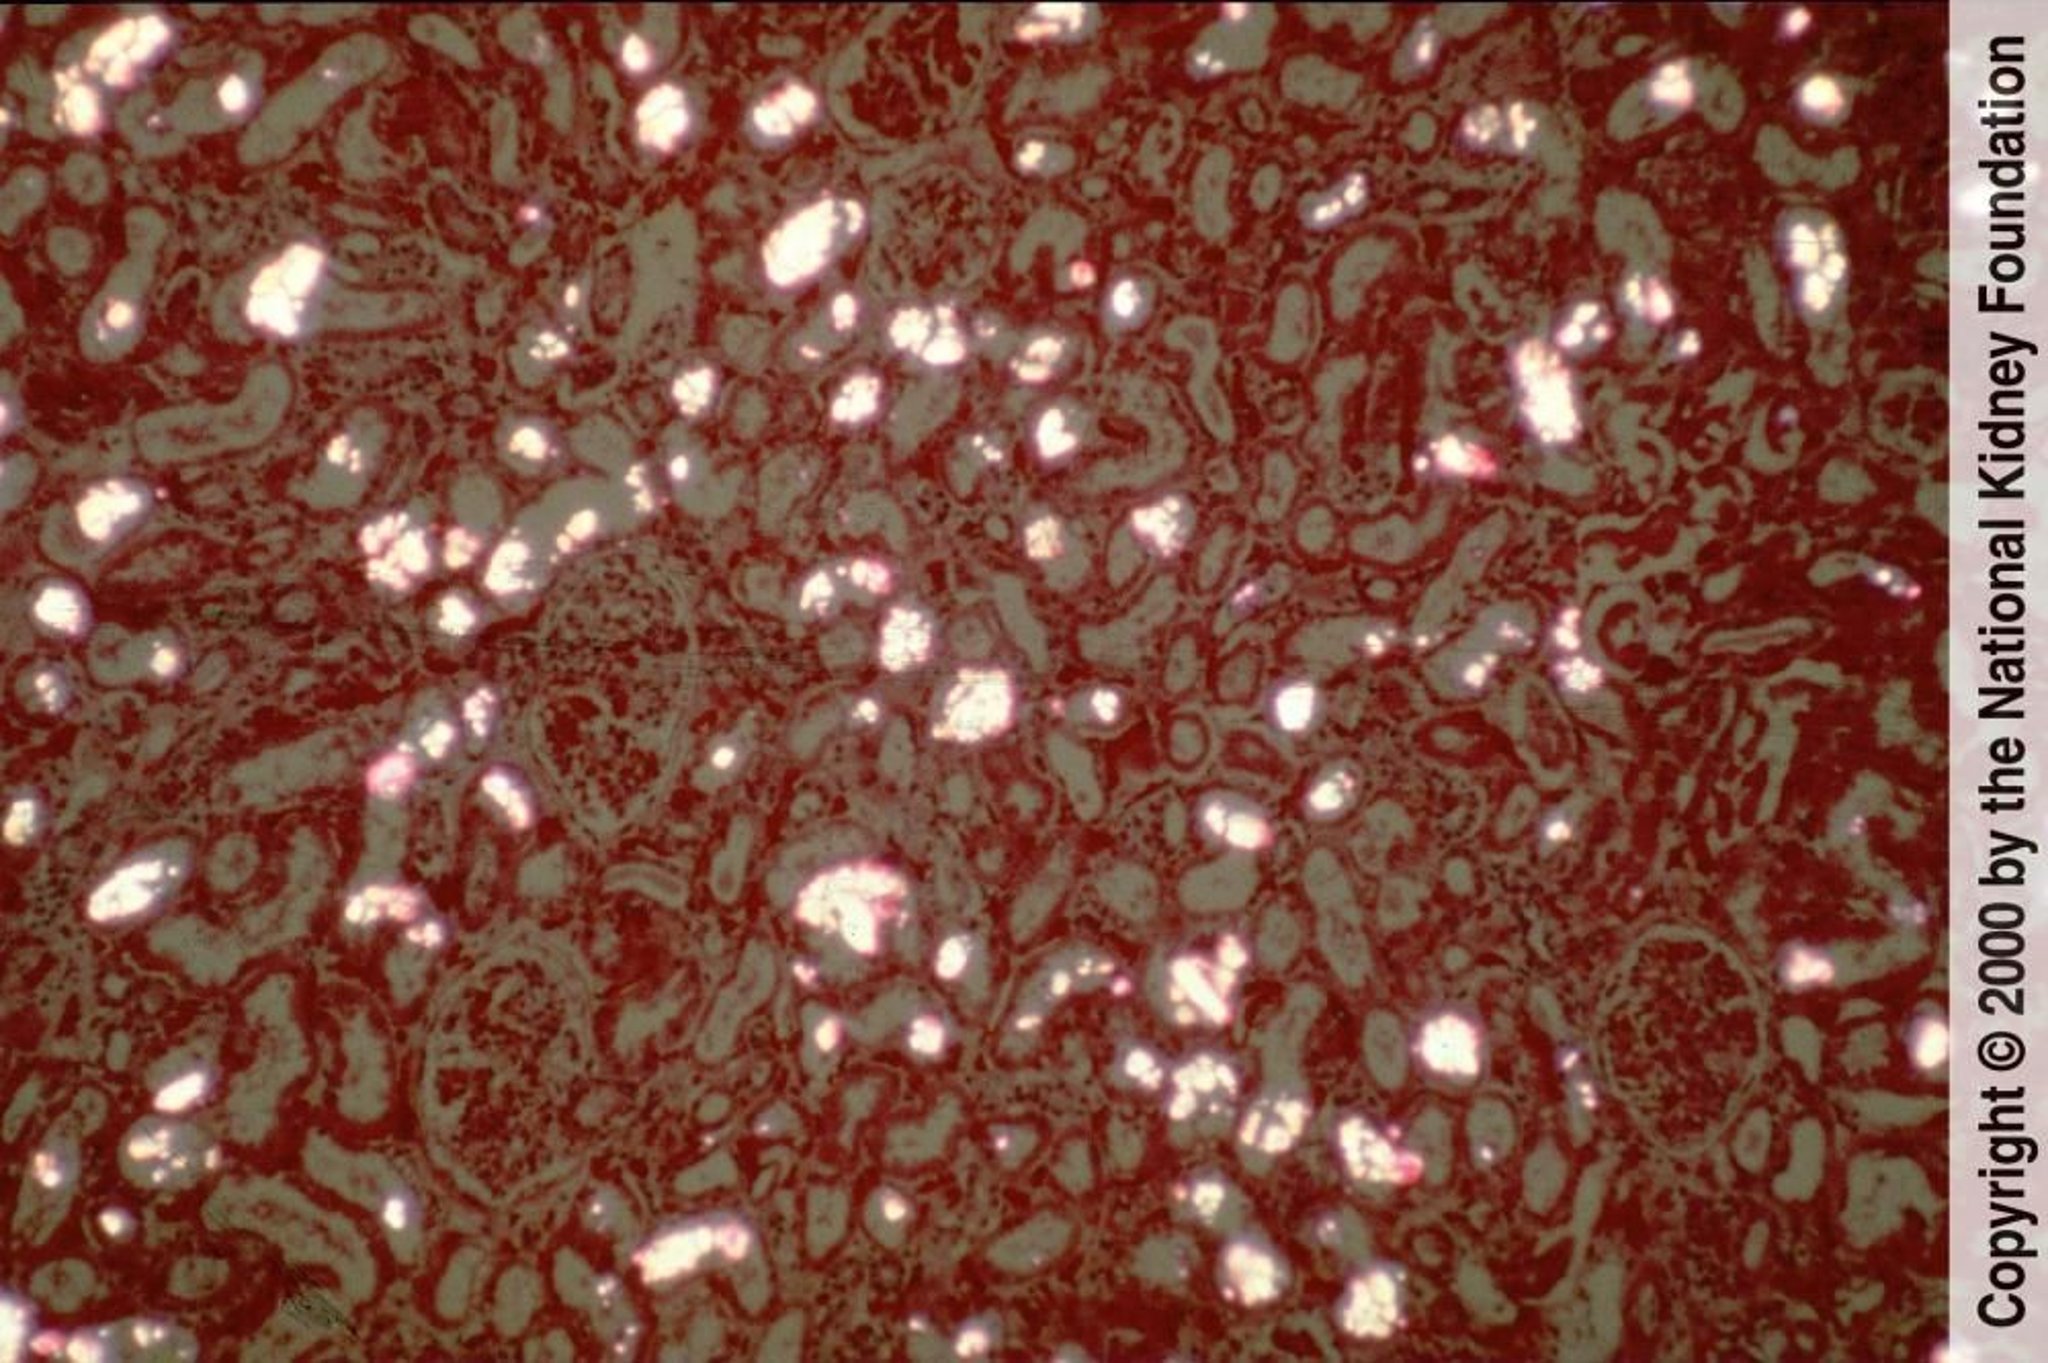

シュウ酸カルシウム結晶が尿細管に沈着し,偏光下では複屈折性の扇型または束型の結晶として容易に観察することができる(偏光ヘマトキシリン-エオジン染色,100倍)。